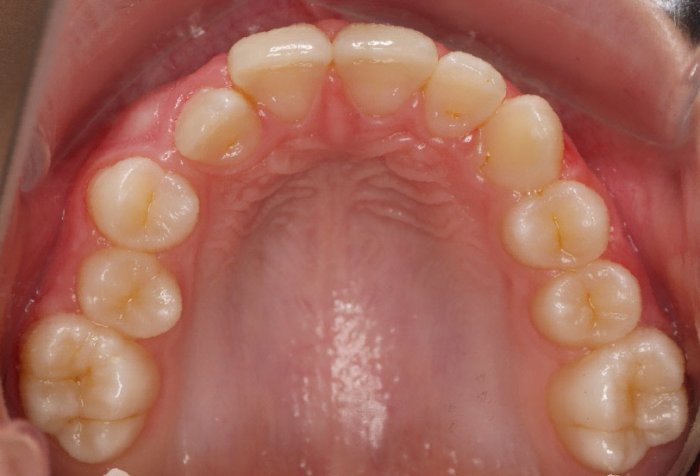

El paciente A.J. de 11 años, acude a nuestra consulta con apiñamiento maxilar importante. El canino lateral (12) está en mordida cruzada. Presenta una Clase II molar y canina, y la línea media está desviada. Se realizó un tratamiento con brackets autoligables metálicos de smartclip 022. La duración del tratamiento fue de 22 meses.

El paciente actualmente ha terminado el tratamiento con brackets y lleva una contención fija de 2-2 en maxilar y 3-3 en mandibular; para complementar también lleva una férula ESSIX durante la noche.